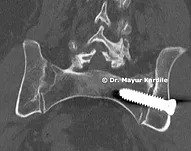

Sacroiliac Joint Fusion

Minimally Invasive SI Joint Fusion

Minimally invasive SI joint fusion surgery for chronic sacroiliac joint pain that hasn't responded to conservative treatment.